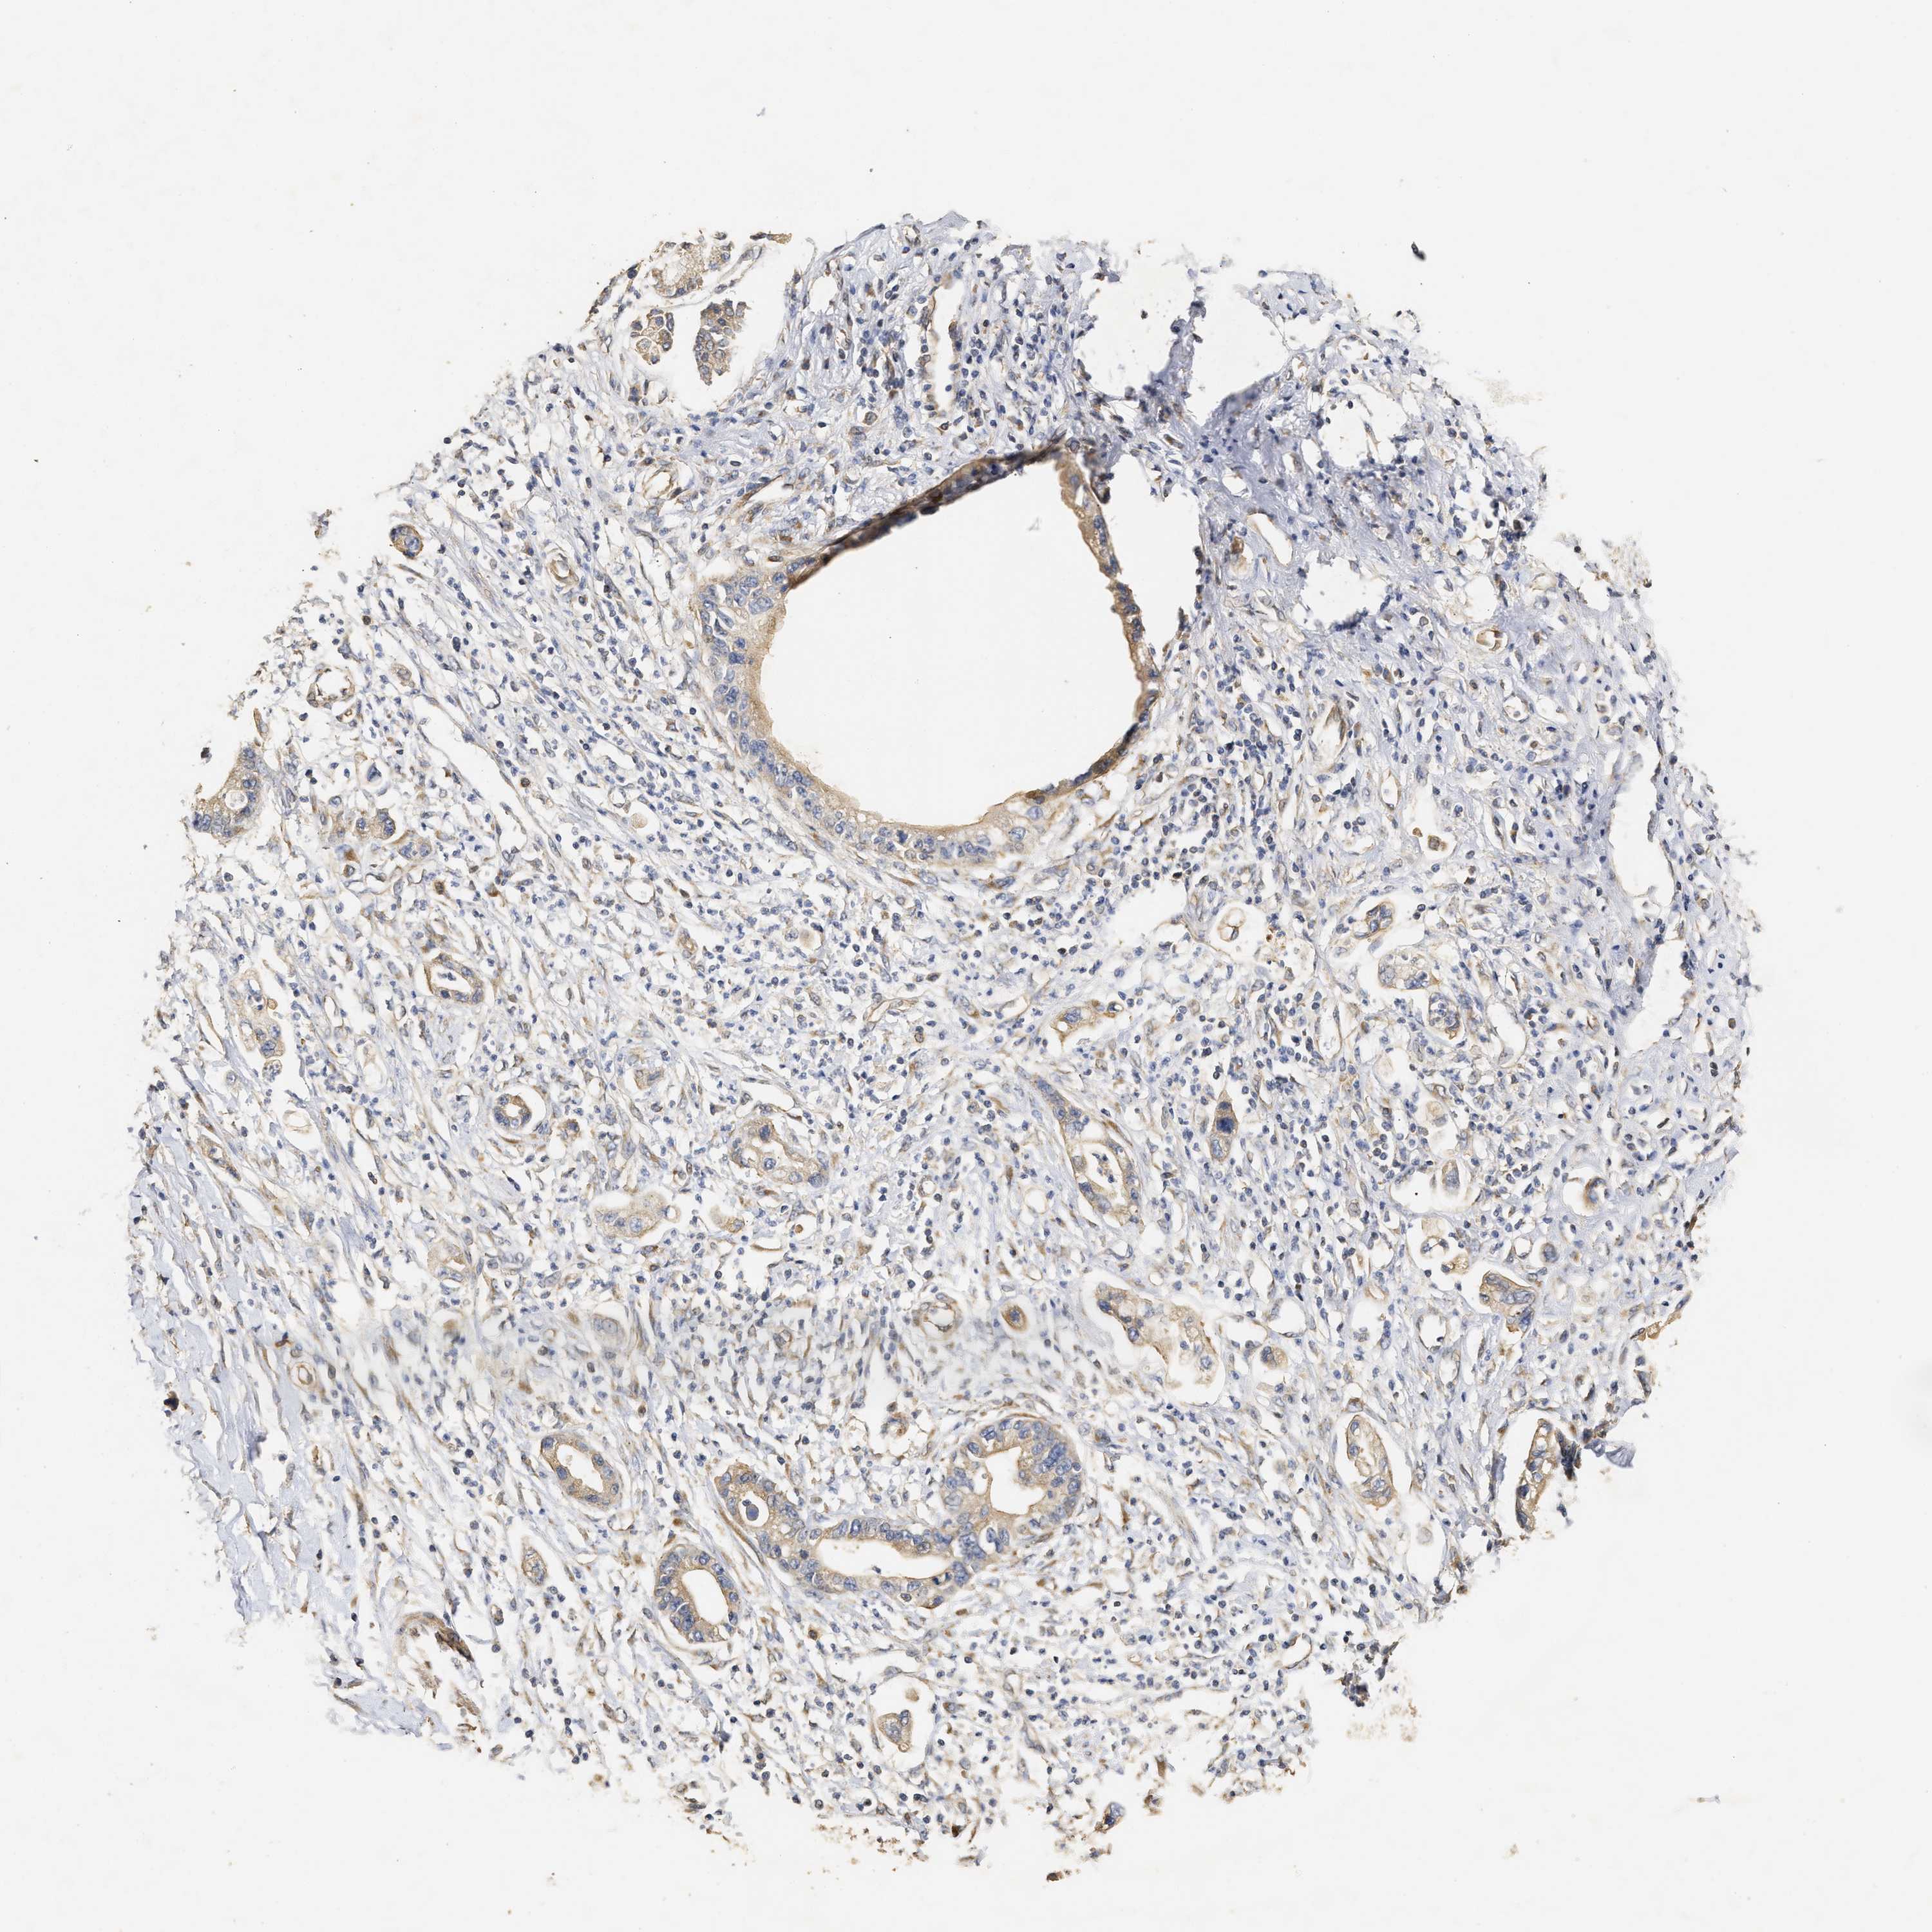

PANCREATIC CANCER - Protein expressioni

A mouse-over function shows sample information and annotation data. Click on an image to view it in a full screen mode. Samples can be filtered based on level of antibody staining by selecting one or several of the following categories: high, medium, low and not detected. The assay and annotation is described here.

Note that samples used for immunohistochemistry by the Human Protein Atlas do not correspond to samples in the TCGA dataset.

Antibody stainingi

Antibody staining in the annotated cell types in the current human tissue is reported as not detected, low, medium, or high, based on conventional immunohistochemistry profiling in selected tissues. This score is based on the combination of the staining intensity and fraction of stained cells.

Each image is clickable and will lead to virtual microscopy that enables deeper exploration of all samples and also displays staining intensity scores, fraction scores and subcellular localization as well as patient and tissue information for each sample.

Antibody HPA018127

Antibody HPA027887

Antibody CAB012302

Adenocarcinoma, NOS

Adenocarcinoma, metastatic, NOS